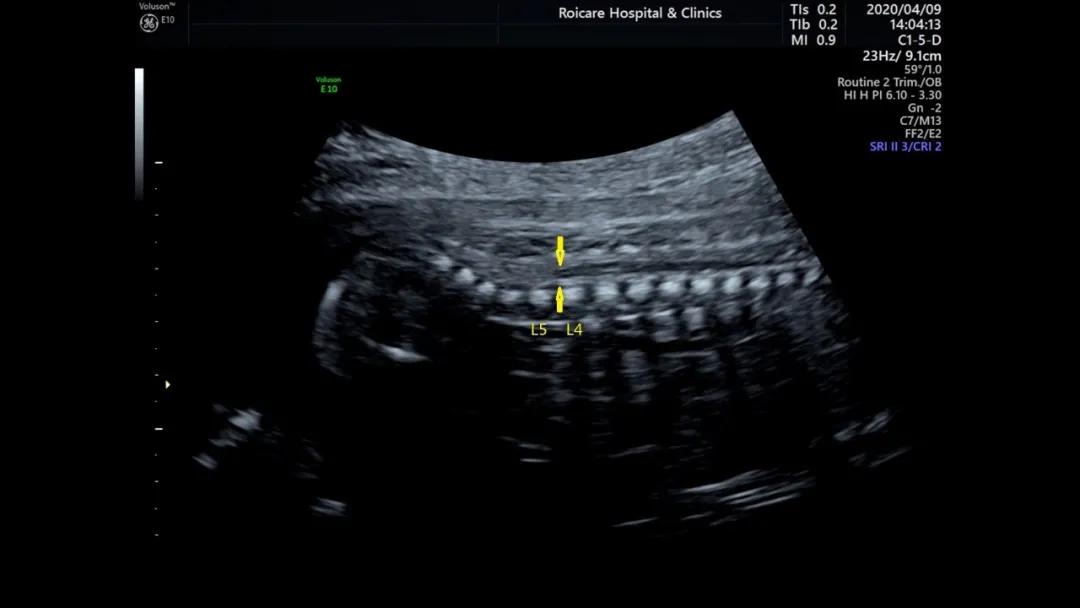

正常位置的脊髓圆锥

出生时脊髓圆锥位于第2腰椎(L2)至第3腰椎(L3)水平,出生后3个月位于L1~L2水平,与成人相同。脊髓下端因各种先天或后天原因受制于椎管的末端不能正常上升,使其位置低于正常,由此而导致的一系列临床神经功能障碍和畸形的综合征即称为脊髓拴系综合征。

正常孕20周以上的胎儿脊髓圆锥的位置达到L3水平以上,如果孕20周以上胎儿脊髓圆锥位置在L4以下,要警惕脊柱裂可能以及是否合并其他异常。中孕期产前超声检查可以发现严重的开放脊柱裂。闭合性脊柱裂表现多样、脊柱裂口小、影像学表现不典型,因此产前超声诊断困难。

脊髓圆锥低位